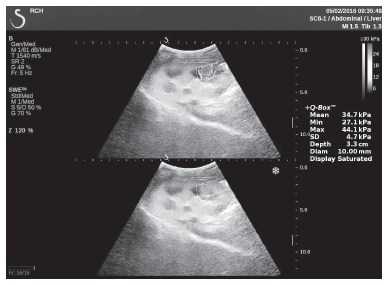

Клинический пример из первой группы. Пациент М., с хронической почечной недостаточностью. Трансплантация почки произведена от живого родственного донора. Трансплантат находится в правой подвздошной области. При нормальном функциональном состоянии трансплантата, показатели цветовой и спектральной допплерографии оценивались как удовлетворительные, с индексом резистентности не более 0,60 (рис. 1); показатели жесткости паренхимы почечного трансплантата при УЭСВ на различных участках составили от 20,05 до 29,18 кПа (рис. 2-4).

Клинический пример из второй группы. Пациент К. перенес операцию пересадки почки от живого родственного донора. Трансплантат в левой подвздошной области. Индекс резистентности в междольковых артериях составил 0,70 (рис. 5). В сегментарных артериях индекс резистентности составил 0,66 (рис. 6). Показатели жесткости паренхимы почечного трансплантата при режиме УЭСВ составили от 31,6 до 36,9 кПа (рис. 7-9).

Рисунок 8. Исследование в режиме ультразвуковой эластографии сдвиговой волны у пациента К.: жесткость паренхимы в зоне нижнего полюса почечного трансплантата 34,7 кПа

Рисунок 9. Исследование в режиме ультразвуковой эластографии сдвиговой волны у пациента К.: жесткость паренхимы у верхнего полюса почечного трансплантата 31,6 кПа